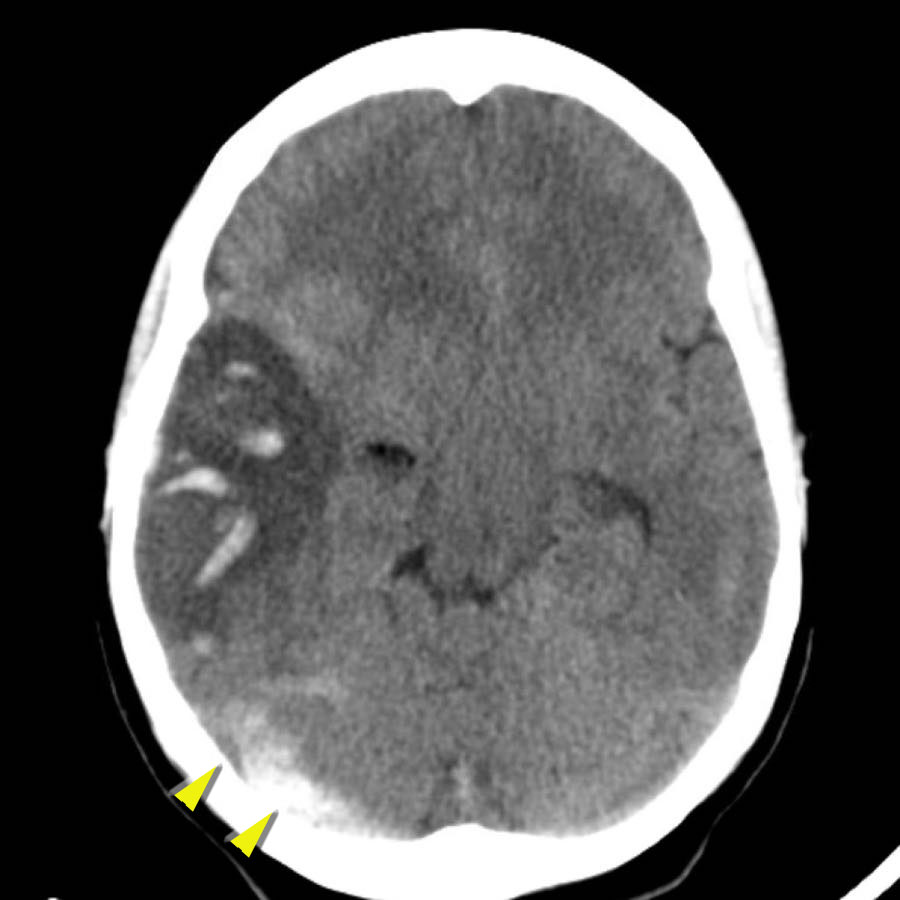

Dưới đây là một số ví dụ về xuất huyết thùy não.

Chảy máu vào hệ thống não thất trong xuất huyết thùy não ít phổ biến hơn so với xuất huyết do tăng huyết áp do vị trí ngoại vi hơn.

Chỉ khi tổn thương rất lớn mới có thể gây chảy máu vào hệ thống não thất (hình).

Bệnh nhân này tử vong vào ngày hôm sau.

Không có chẩn đoán xác định nào được đưa ra, nhưng được cho là trường hợp CAA.